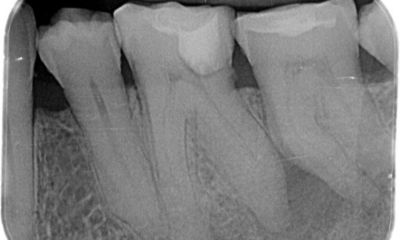

Review different horizontally angulated radiographs to diagnostically determine the width, length, and curvature of any given root canal.

Estimate the working length using well-angulated preoperative radiographs.